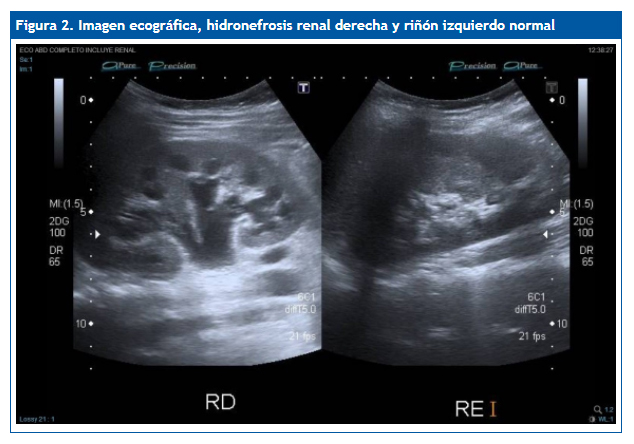

Ante los vómitos y la exploración abdominal se solicitaron: sedimento de orina pH 5, densidad 1030, hematíes 150/µl, proteínas 75 mg/dl, uratos amorfos; hemograma normal; química (función renal, proteínas totales, albúmina, electrolitos incluyendo Na, K, Cl, Ca, Mg, fósforo) normal; urinocultivo negativo; coprocultivo y virus en heces negativo; radiografía de abdomen normal, no se visualiza imagen de litiasis; ecografía abdominal (Figs. 1 y 2): cálculo de 7-8 mm, casi en el meato ureteral derecho, a 5-6 mm de la vejiga, con moderada ureterohidronefrosis proximal. No había líquido libre intraperitoneal. No se observa apéndice engrosado. El riñón y la vía excretora urinaria izquierdos no mostraban alteraciones.

La ecografía ha supuesto un gran avance en el diagnóstico de los cálculos, especialmente en niños, en los que suelen ser de pequeño tamaño. El aspecto típico es el de una imagen hiperecogénica con sombra sónica posterior.